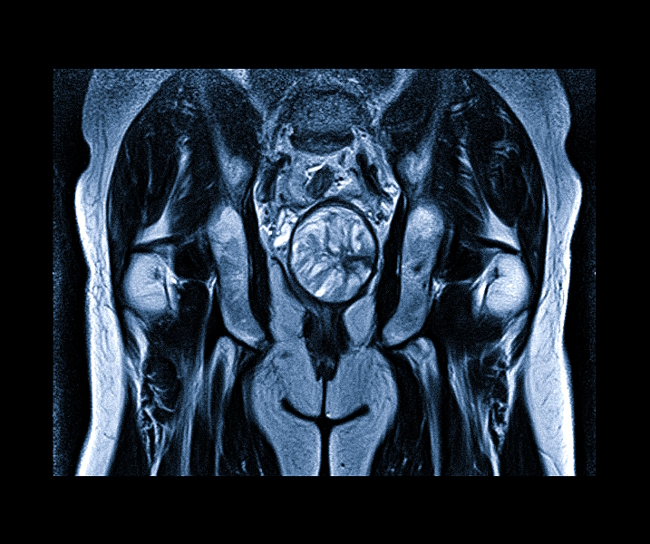

Магнитно-резонансная томография МРТ позволяет визуализировать мягкие ткани тела, используется для диагностики патологических процессов в мышцах, связках, сухожилиях и прилегающих структурах организма.

Когда говорят о «мягких тканях» применительно к МРТ, под этим термином обычно подразумевают мышечную ткань, подкожно-жировую клетчатку, связки, сухожилия, фасции*, сосуды, нервы и лимфоузлы.

МРТ мягких тканей помогает врачу, например, выяснить причину компрессии нерва или сосуда. Довольно часто проводится МРТ мягких тканей шеи – для определения патологий глотки, гортани, а также щитовидной железы.

МР-томография мягких тканей применяется также для обнаружения рентген-неконтрастных инородных тел, гематом, для изучения структурных элементов суставов, лимфатических узлов, сосудистых сплетений.